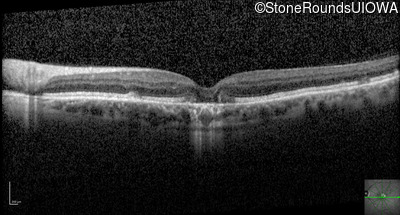

Optical Coherence Tomography - Right - 20/25

Exemplar / OCT Stack